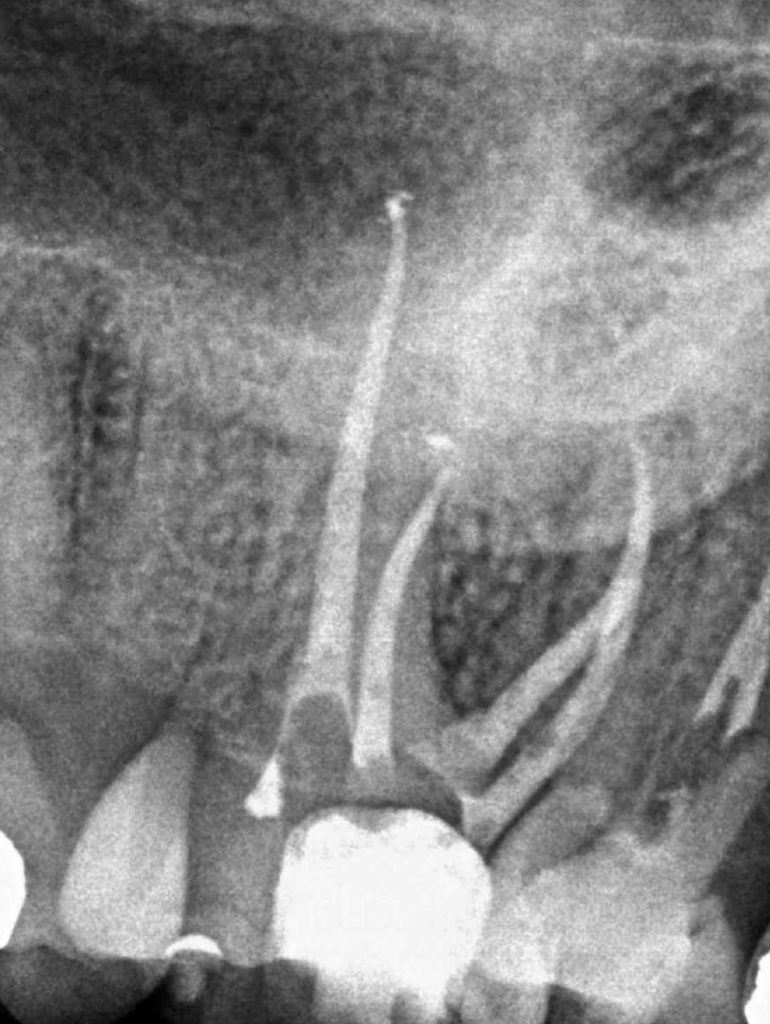

Vertical root fracture